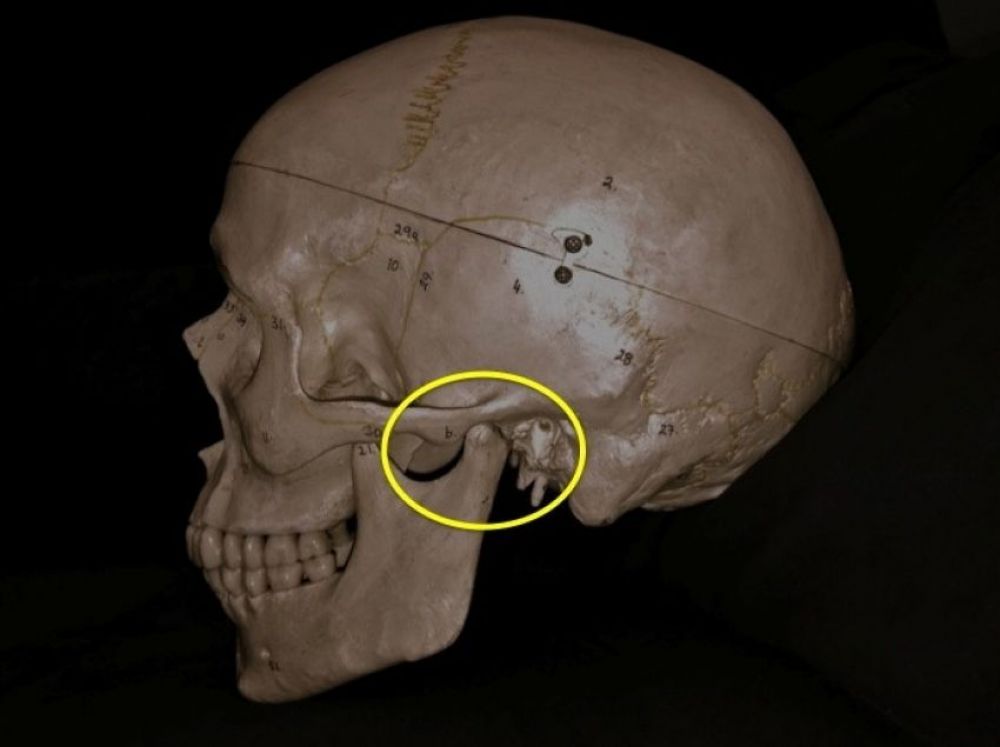

Un porcentaje muy alto de las consultas de Cirugía Maxilofacial, tanto que pueden llegar al 30% de las mismas, se refieren a problemas en la ATM, que es la articulación que une la mandíbula (parte móvil) con el cráneo (parte fija). De ellas, casi todas corresponden a un cuadro que suele tener uno o varios de los siguientes síntomas: dolor en reposo y/o al mover la mandíbula, otalgia (dolor de oído), disminución en la amplitud de los movimientos mandibulares, dolor muscular que puede irradiar al cuello y/o a la parte lateral del cráneo, etc… Casi siempre acompañando a todos o a alguno de esos síntomas, suele asociarse un aumento de la ansiedad y de la tensión emocional, que es la mayoría de las veces quien cierra el circuito desarrollando la explosión de la sintomatología referida. Este complejo de síntomas y signos se denomina Síndrome de disfunción de la ATM.